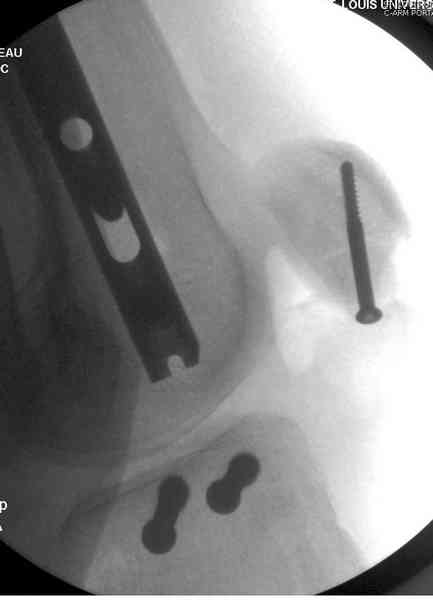

Пострадавшему 21 г., травма скоростная, после I&D с расширением раны, на бедре сделана операция ретроградным интрамедуллярным штифтом, остеосинтез с частичной резекцией надколенника и ушивание собственной связки.

На голень наружный фиксатор, рану на бедре ушили (рана была изнутри кнаружи всего 2 см). По протоколу травматических больных, до операции обследован ангиографически, (у больного дистально не смогли определить пульсацию) сосудистый хирург подтвердил проходимость на всем протяжении магистрального сосуда нижней конечности по снимкам ангиограмм.

В настоящее время больной в реанимации по поводу Черепно Мозговой Травмы и состояние улучшается. Запланировал ушивание раны в пятницу, если позволит состояние мягких тканей и при отсутстви отека возможно удастся просунуть перкутанномедиальную пластину.